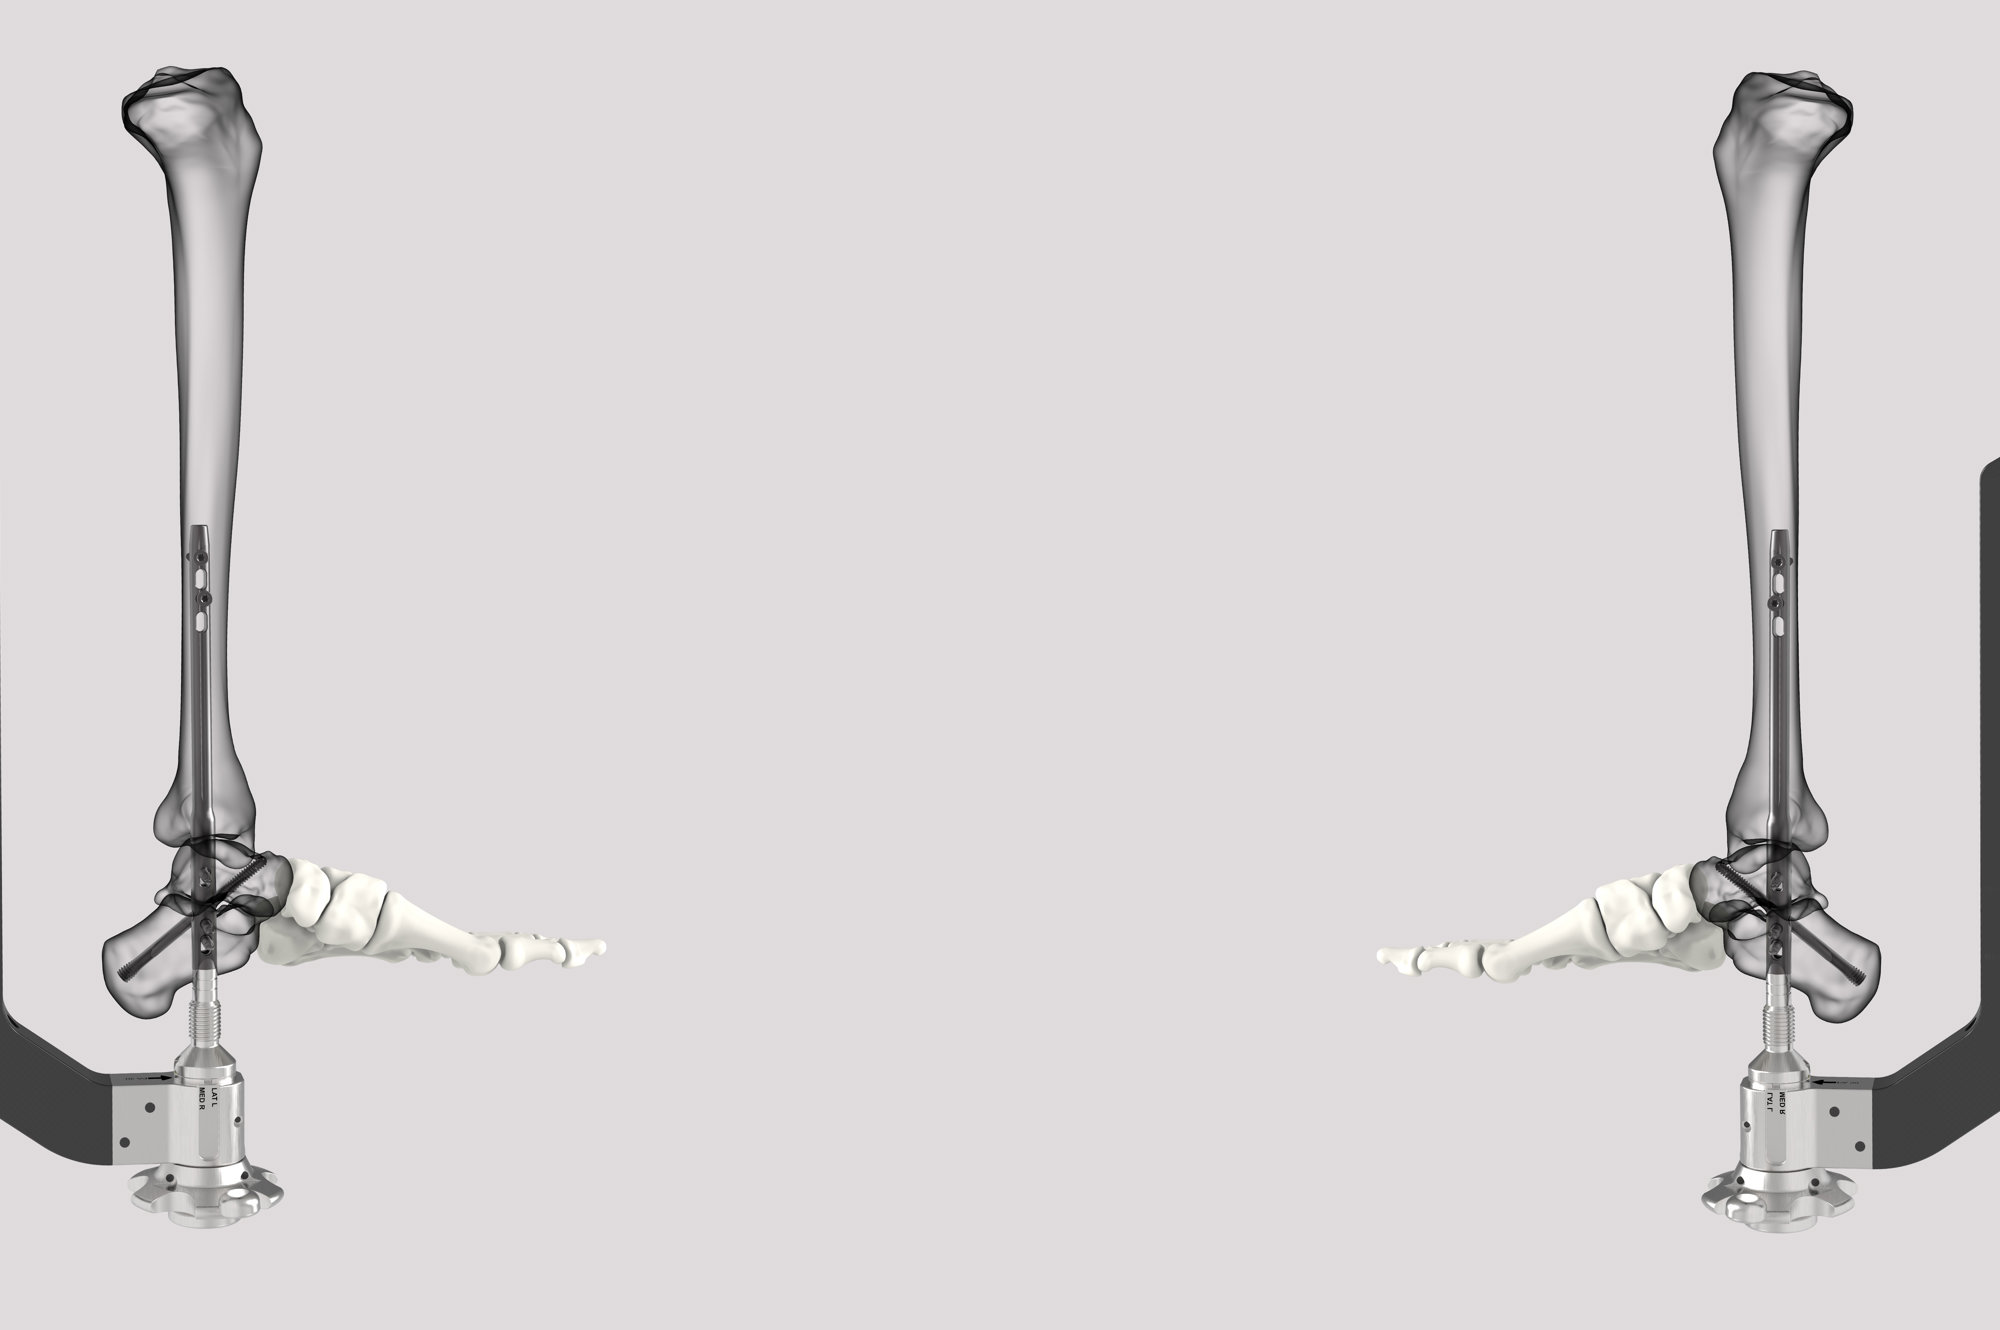

SUCCESSION® TTC Nail System

The SUCCESSION® TTC Nail System provides the surgeon with greater control, allowing for customized treatment based on each patient’s specific needs